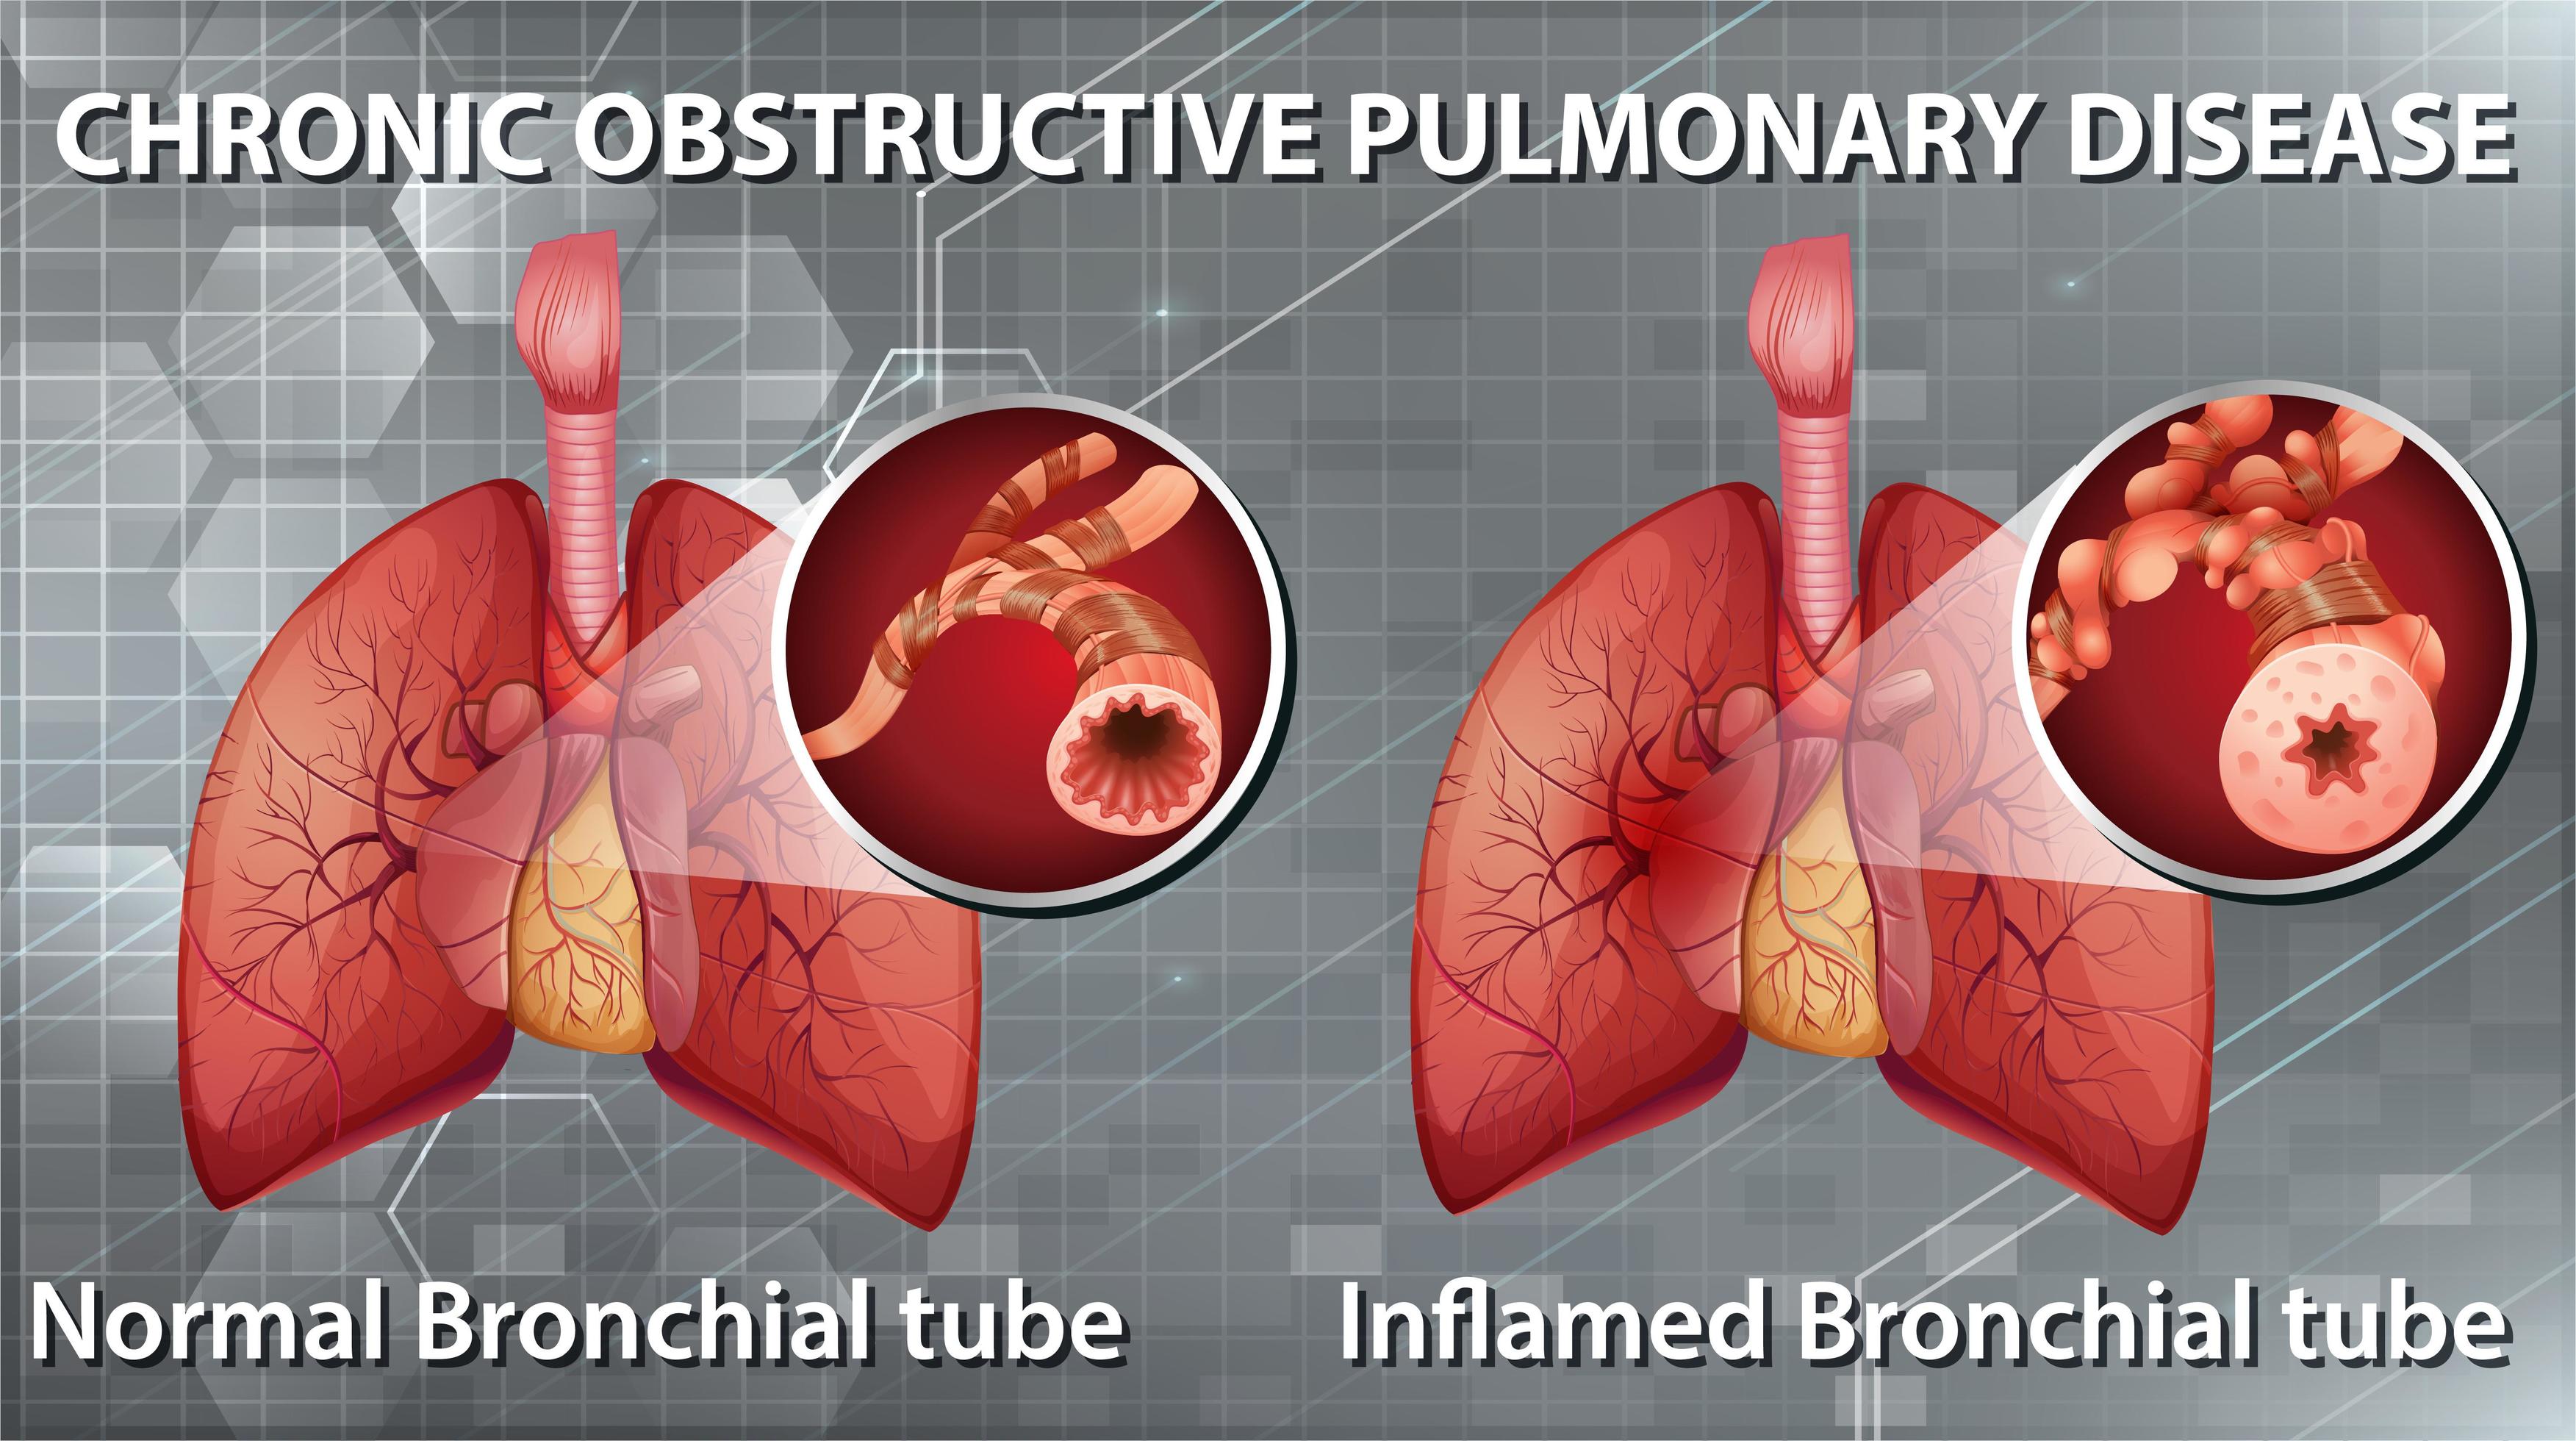

DPOC (doença pulmonar obstrutiva crônica) é um conjunto de doenças respiratórias, como bronquite crônica e enfisema pulmonar, que bloqueiam as vias aéreas e dificultam a respiração. A principal causa da DPOC é o tabagismo, pois a fumaça e outras substâncias presentes no cigarro prejudicam o tecido das vias respiratórias, levando ao.

A doença pulmonar obstrutiva crônica (DPOC) caracteriza-se pela limitação crônica ao fluxo aéreo, não totalmente reversível, associada a uma resposta inflamatória anormal à inalação de partículas ou gases nocivos.

Poluição do ar intra e extradomiciliar. Na DPOC, ocorre inflamação crônica das vias aéreas centrais e periféricas, parênquima e vasos pulmonares em resposta à inalação de partículas e gases nocivos, com acúmulo principalmente de macrófagos, neutrófilos e linfócitos T (sobretudo CD8).